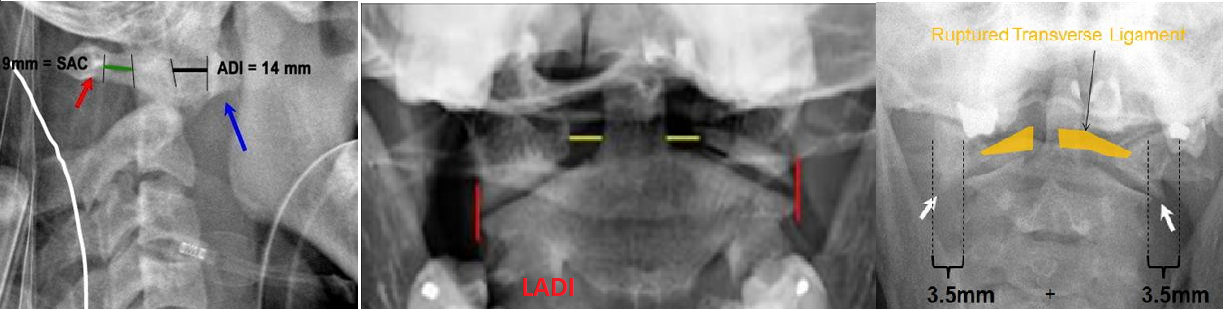

What are the radiographic parameters to assess for atlas fractures?

What are the radiographic parameters to assess for atlantoaxial instability?